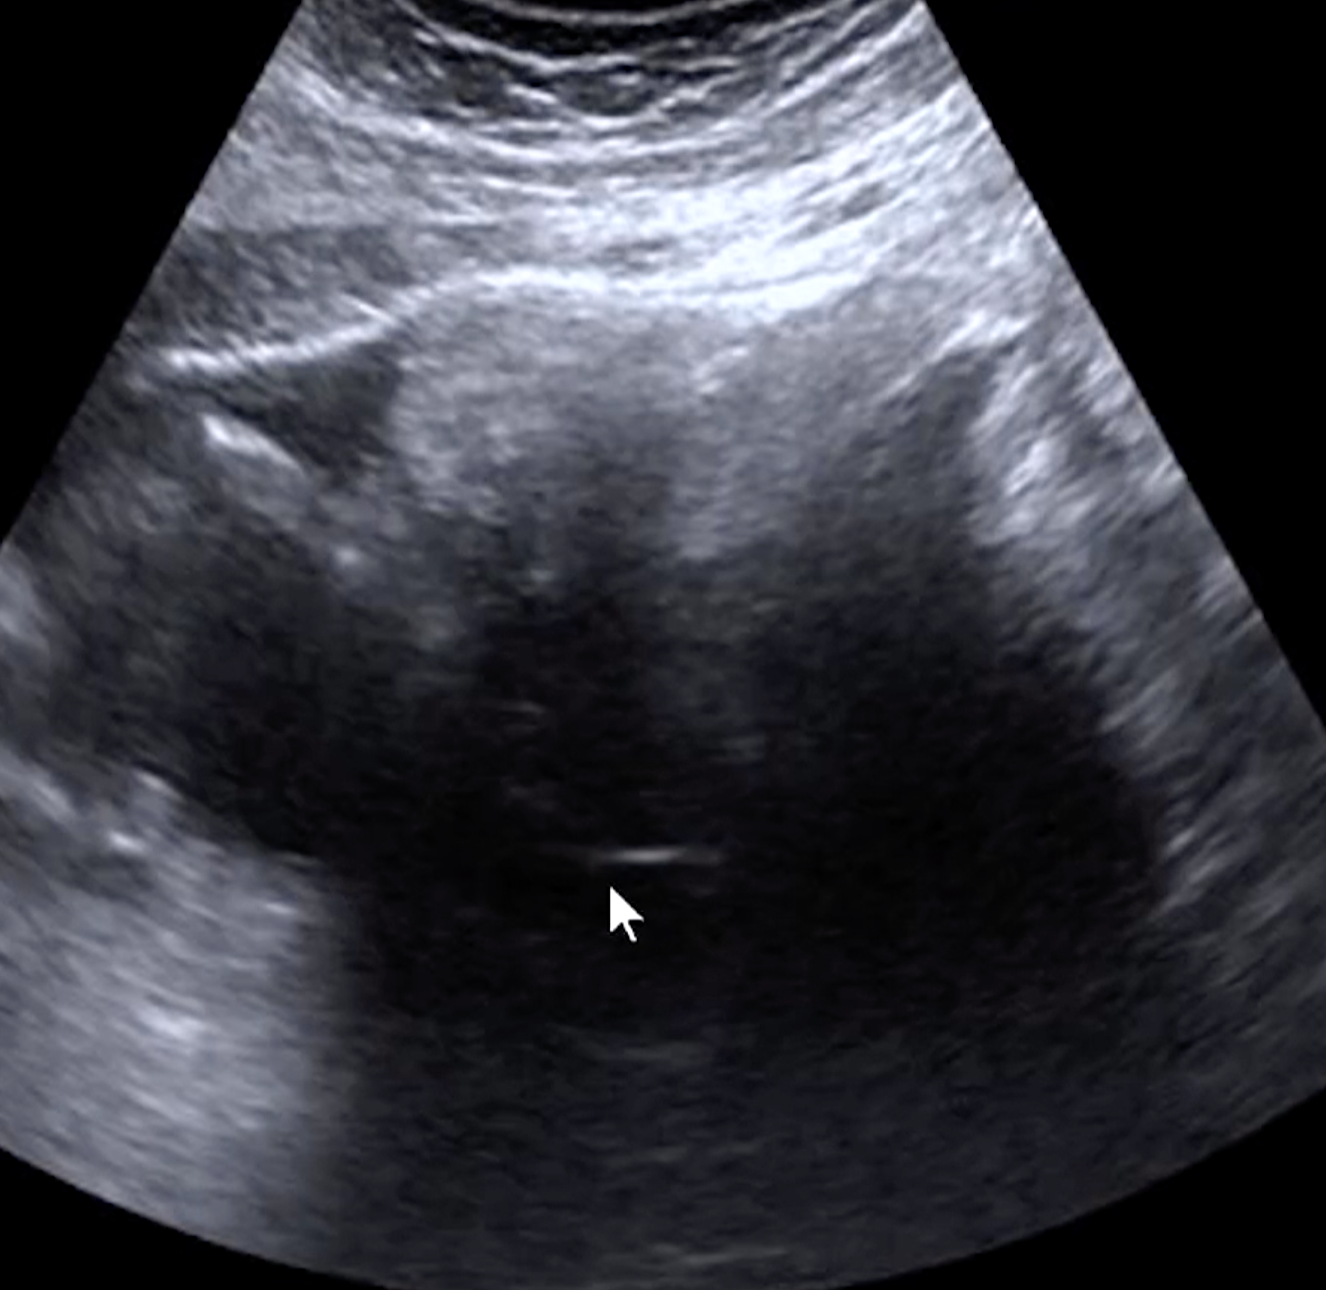

• On Us

• Tip of the iceberg (bottom)

• Broad area of deep hypoechogenicity with iso or hyperechogenic area superficially

• Fluid-fluid level

• High echogenic substance is in anti-dependent portion and fluid is on bottom

• Fat ball sign (top)

• No color on doppler